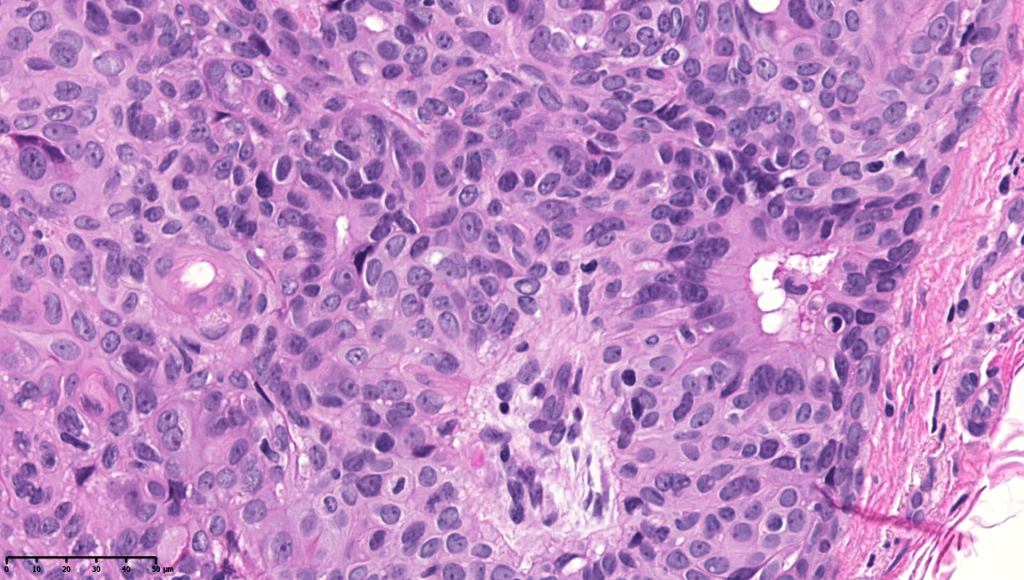

•In poroma, a dermal-centric tumor is associated with epidermal origin/continuity & is composed of small cells with vesical nuclei.

•Desmosomes often prominent

•Clear cells (sometimes predominating- so-called clear cell variant)

•No peripheral palisading or retraction artifact

•Generally few mitoses but occasionally can be conspicuous. In the absence of other features of porocarcinoma, this should not be taken as necessarily implying maligant potential unless other worrying features sre also present (see case below)

•No pleomorphism or abnormal mitoses